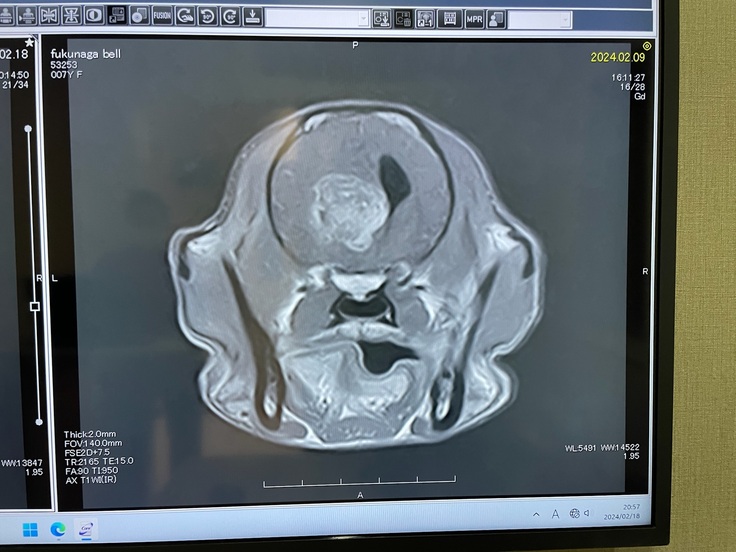

MRI・CT検査の結果、頭の半分程を埋める異物が見つかりました。

てんかん発作の本当の原因がこの異物に隠されていました。

病理組織診断の結果は希突起膠細胞腫。活発で悪性度の強い脳腫瘍

再発の可能性が高いため、早い段階での放射線治療が必要です。